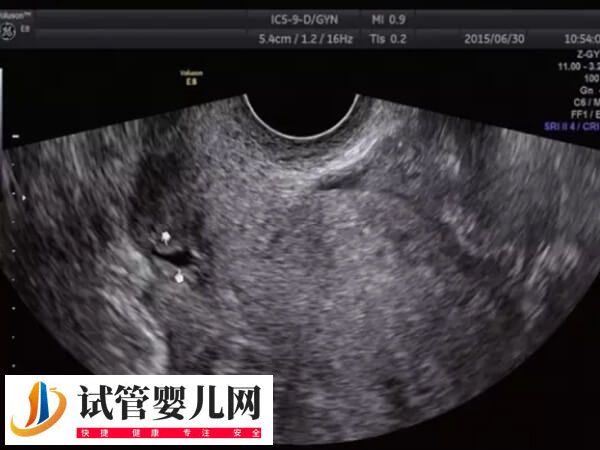

子宫憩室一般也叫剖宫产切口憩室或者子宫切口瘢痕缺损,主要是因为剖宫产手术遗留的刀口组织恢复不佳,从而造成的一个子宫凹陷空间。女性出现子宫憩室时,通过试管婴儿技术助孕怎么样,可以参考下列内容:

不过因个体之间存在较大的差异,所以子宫憩室能否做试管婴儿,还需要根据患者的年龄、症状、既往妊娠并发症、子宫腔的状态、憩室的大小、疤痕处的肌层厚度等多方面进行判断,患者可以直接前往医院咨询相关医生即可。